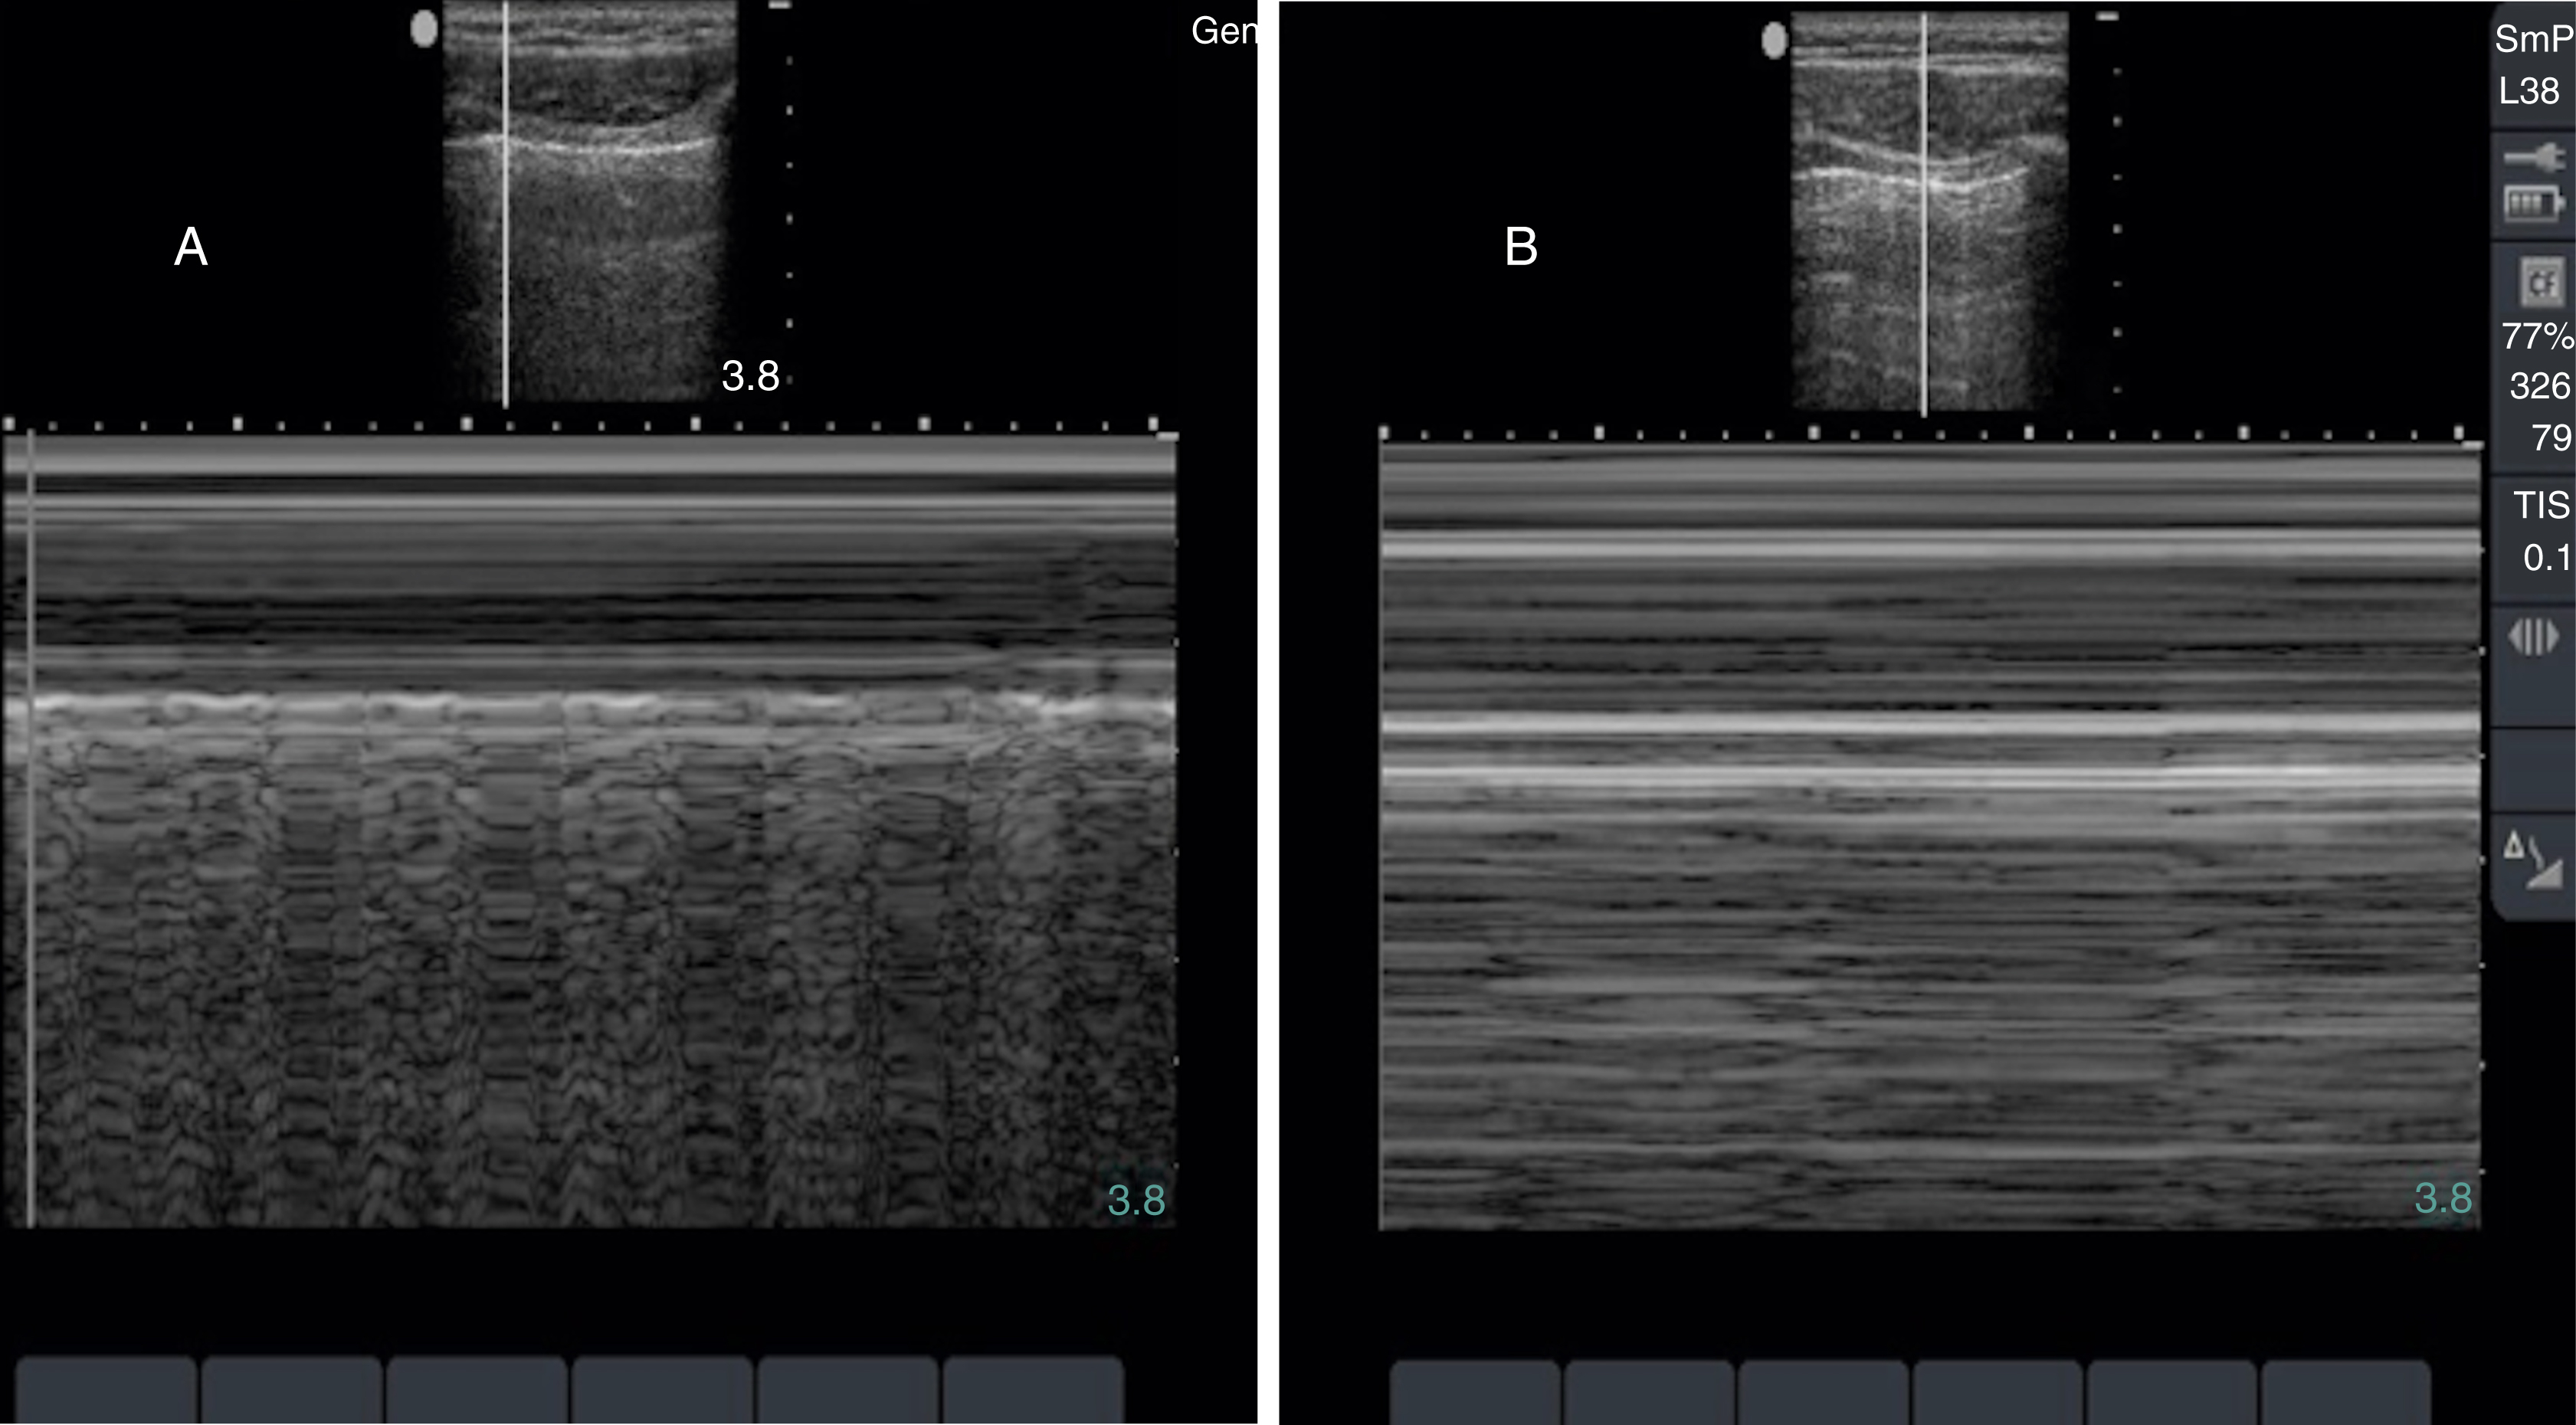

Pathology

Hydronephrosis is characterized by dilation and anechoic fluid accumulation within the renal pelvis and calyces, ranging from mild to severe ( Fig. e3.6 ). Renal and/or ureteral calculi may be identified as echogenic foci with associated shadowing and are usually located within the kidney (nonobstructive) or in the renal pelvis, proximal ureter, or uretero-vesicular junction. Color Doppler placed over the kidney can help differentiate mild hydronephrosis from the renal vasculature, as well as possibly accentuate any renal stones by producing the renal twinkle artifact.

Fig. e3.6

Hydronephrosis with dilation of the calyces and renal pelvis of the kidney showing thinning of the cortex, signifying severe hydronephrosis.